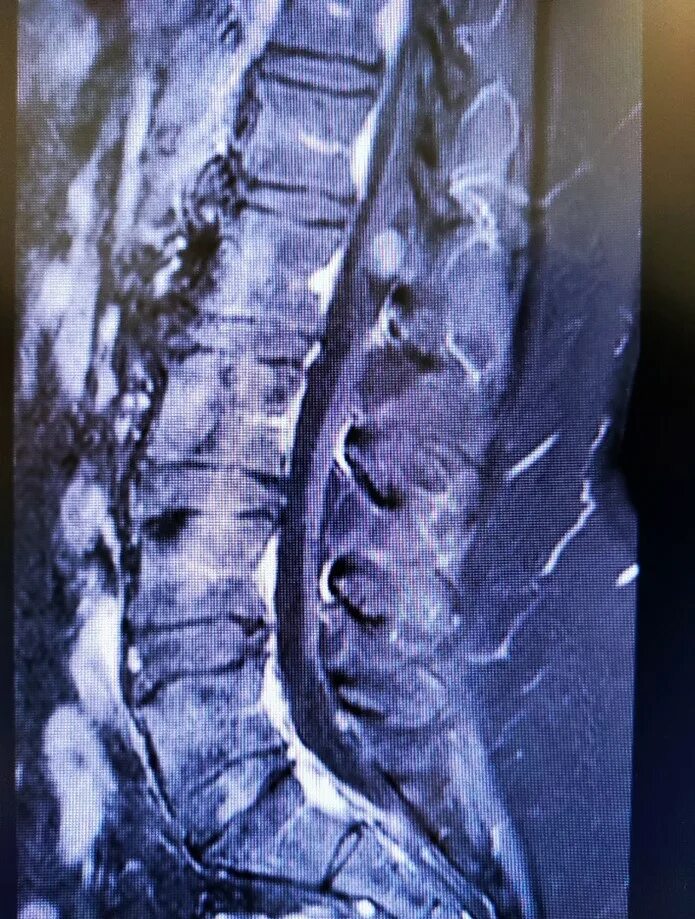

Деформация дурального мешка поясничного